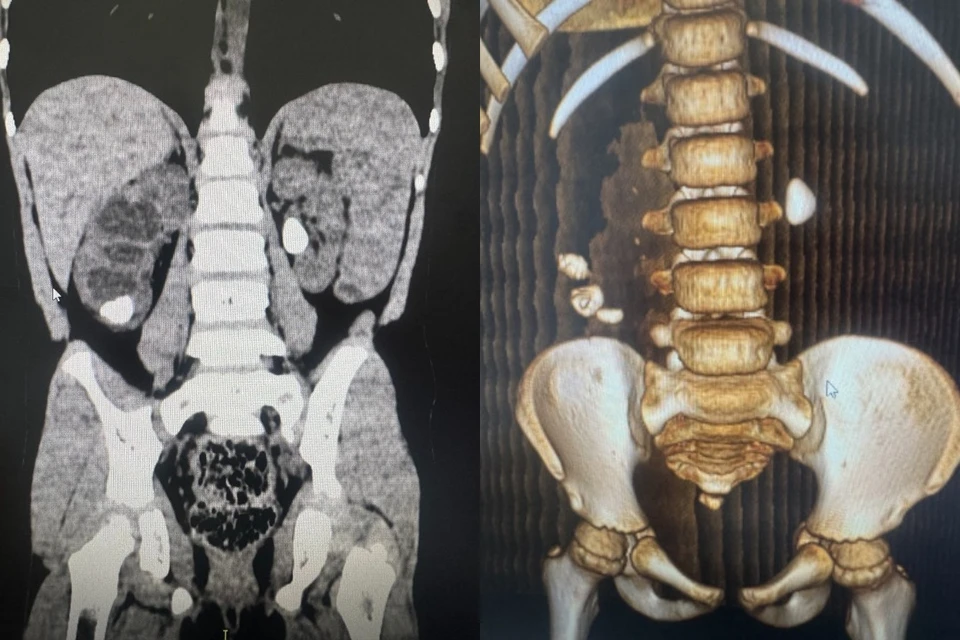

В Новосибирской области наблюдается настораживающая тенденция – количество детей и подростков с мочекаменной болезнью постоянно растет. Так, только в детской городской клинической больнице №1 в 2024 году лечились 82 ребенка с таким диагнозом, а в 2025-м хирурги удалили камни у 118 детей. Об этом сообщили в региональном Минздраве.

- Самому юному нашему пациенту было всего 7 месяцев. Он был из недоношенной двойни. При рождении у него масса была 1200 граммов. В развитии мочекаменной болезни иногда играет роль незрелость ребенка при рождении, - рассказала детский хирург и уролог Ирина Живолуп.